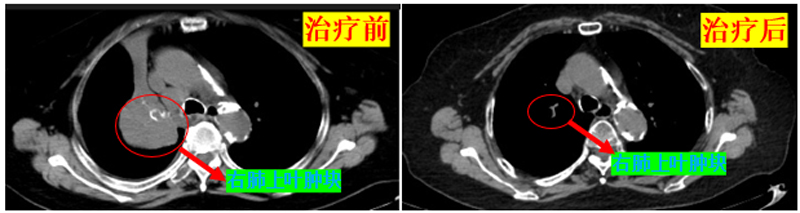

治疗前后患者的肿瘤改变

经过数个周期的化疗治疗,患者的肿瘤显著缩小,身体状况明显好转。她的顽强意志和医护团队的默契配合,使得原本看似绝境的情况逆转为希望的曙光。